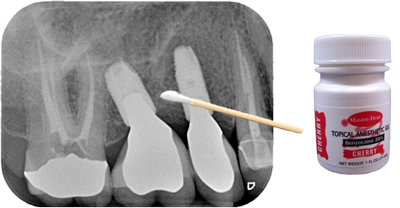

Finding and Blocking a Trigger Zone using a Q-tip Test

When a patient is complaining about pain and the teeth have been ruled out as a cause, the dentist should see if he/she can find the trigger zone and replicate the pain using a Q-tip. First, ask the patient to describe where the pain is occurring and, even better, give them a Q-tip to show you where they are feeling pain. Then using a very light touch with the Q-tip, try stroking the tissue around the area where the patient is reporting their pain and ask them if that hurts. Then try pressing on the same area with firm pressure in various different spots and ask them if that hurts. If you are able to replicate the pain using either of these techniques then the next step is to see if you can reduce or block the pain. Apply a topical anesthetic to the area where you caused the pain with a Q-tip. Wait a few minutes and repeat the Q-tip test to see if you can replicate the pain. Next, try infiltrating the papilla or local tissue where you were able to replicate the pain and repeat the Q-tip test. Last, try blocking the tooth as if you were going to do a restoration and repeat the Q-tip test. If you have ruled out an odontogenic cause of the pain, and any of these methods greatly reduce or block the pain, then it is likely a neuropathic pain of the trigeminal nerve. If you cannot block any of the pain, then the pain is centralized. The next step, especially in the case of pain on the maxillary arch, is to try is a sphenopalatine ganglion block (SPG). This can be done in the office. I use a Sphenocath with 2 cc’s of 4% lidocaine into the nostril on the ipsilateral side of the pain. If you can block the pain using an SPG block, repeat the procedure once a week for a total of six weeks. This will hopefully provide the patient with pain relief for six months or longer.

An important piece of this pain puzzle to keep in mind is if the pain started on its own or if the pain started after a dental procedure or any trauma. If it started on its own, is intermittent, and is described as a sharp, shooting, electrical pain then it is likely trigeminal neuralgia, which can be treated with anti-seizure medications and an MRI must be ordered. If the pain started after a dental procedure, you have ruled out the tooth, is described as a painful, sharp, shooting and/or burning pain that does not go away, and you can reduce the pain or completely block it, then it is likely a post-traumatic trigeminal ​neuropathic pain (​PTNP), which can be treated topically.